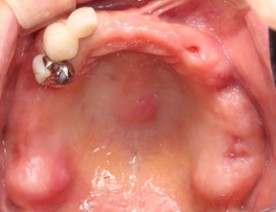

40代 女性

- リスク・副作用

- 術後疼痛、歯肉腫脹

- 治療の費用

- 合計¥686,000(税込)

【内訳】

インプラント(1本) ¥440,000

その他費用¥246,000

(薬・注射・レントゲン・CT・データ分析・骨造成・サージカルステント・血液検査) - 年齢/性別

- 40代/女性

- 患者の具体的な症状

- 左上6欠損のため義歯を使用していたが、噛むと痛みがあり不快なため、インプラント治療を希望

- 検査方法

- コーンビームCT、レントゲン撮影

- 診断結果

- 左下6欠損

- 治療詳細

- コーンビームCTによる画像診断で垂直的な骨高が不足し骨密度が少ないため、ソケットリフトによる骨再生治療とインプラント埋入を同時に行った。

- 通院回数

- 7回

- 治療期間

- 7か月